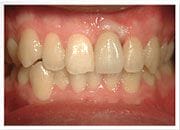

治療前